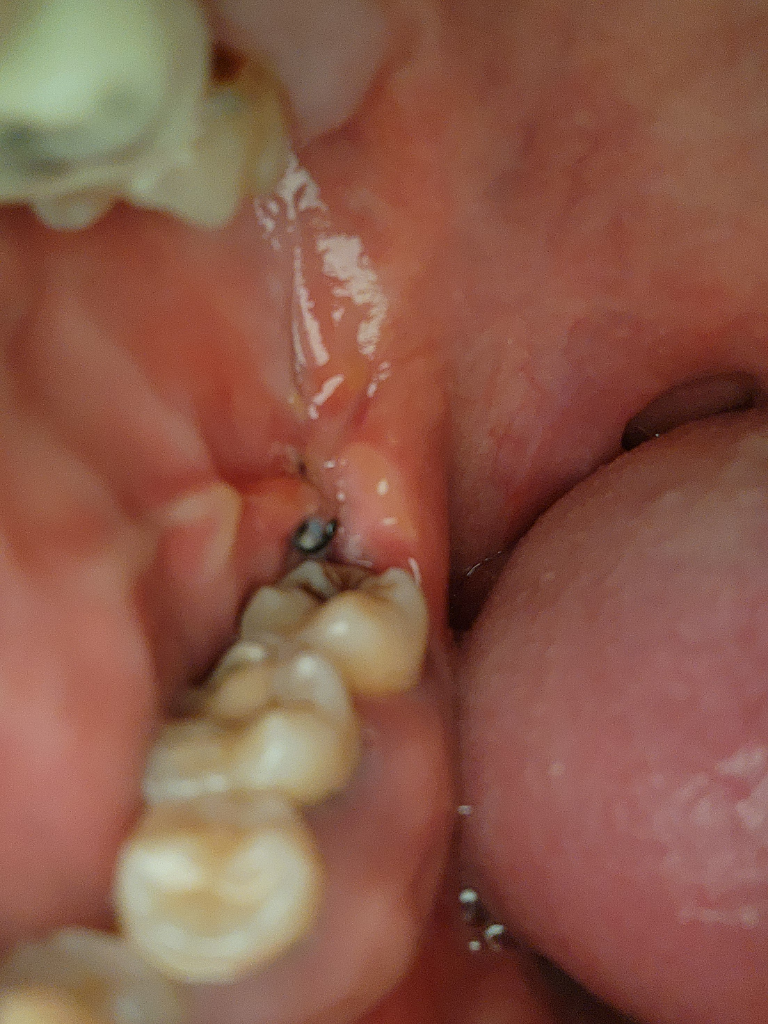

어제께 매복사랑니 발치 햇는데요 지금 잘 낫고 잇는건지 염증이 생긴건지모르겟네요 실주위에 하얀거 멀까요? 궁금합니다 알려주세요

사진상으로 보면 크게 문제가 잇는건 없어 보입니다. 상처가 낳으면서 자연스럽게 생기는 현상이니 물로만 잘헹궈주시면될것같습니다.

하얀막은 상피세포가 생기는 단계이며 통증이 심하거나 냄새가 심한 등 증상이 없다면 괜찮습니다.

현재 사진상으로 잘 아물고 있는 것으로 보이기에 걱정하지 않아도 됩니다. 치료부위에 염증이 생기지 않도록 소독용 헥사메딘 가글액 사용을 권합니다.